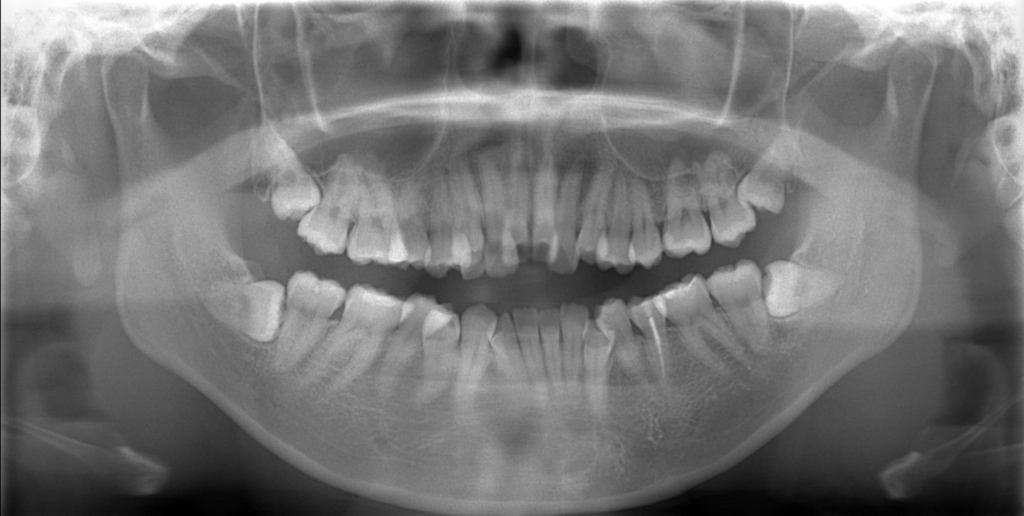

レントゲン写真で確認すると、

この患者さんの場合、

#1.顎と歯の不調和による叢生(重度)

#2.上顎前突(出っ歯)

#3.開口

と診断しました。